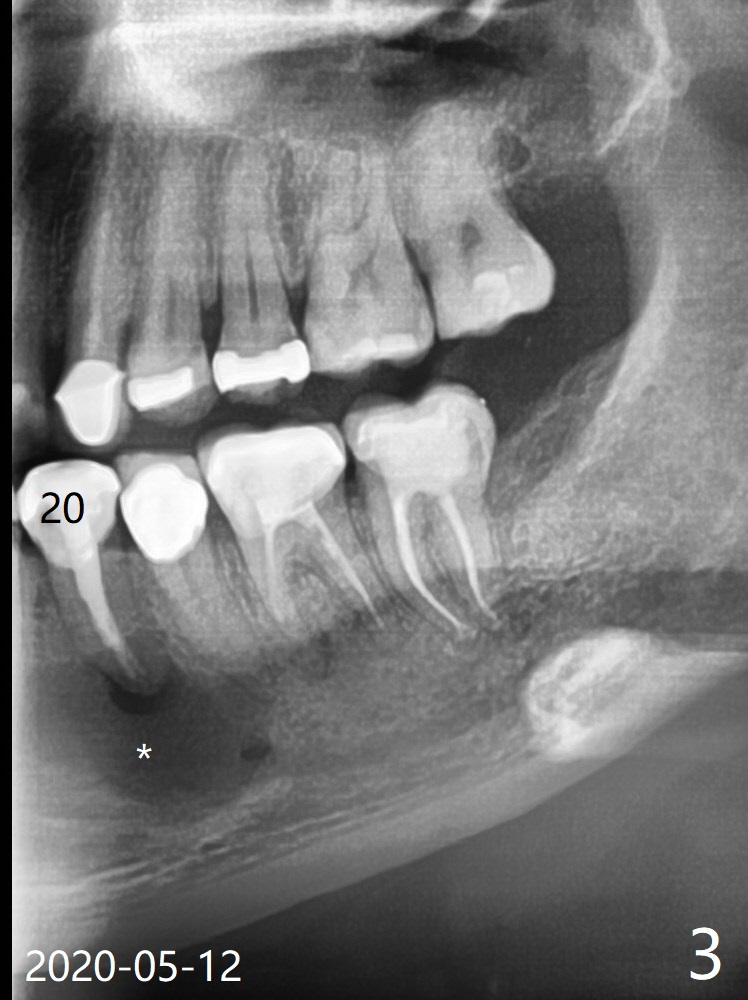

A 37-year-old man complains of food impaction between #14 and 15, which may be related to mesioangular impaction of #16 (Fig.1 ^ (* a supernumerary premolar; #20 asymptomatic after RCT retreatment)). When the third tooth is removed, it is smaller than expected. Intraop X-ray reveals a normal sized 3rd molar in situ (Fig.2 ^). Therefore the microdontia removed is a supernumerary tooth. The tooth #16 is then extracted. The diastema appears to persist 2 years 7 months postop (Fig.3), although gingival swelling and pain reduces. There is a significant increase in PARL at #20, supported by 2 PAs (Fig.4,5). The tooth has no mobility with normal periodontal pockets. There is no paresthesia of the lower left lip.